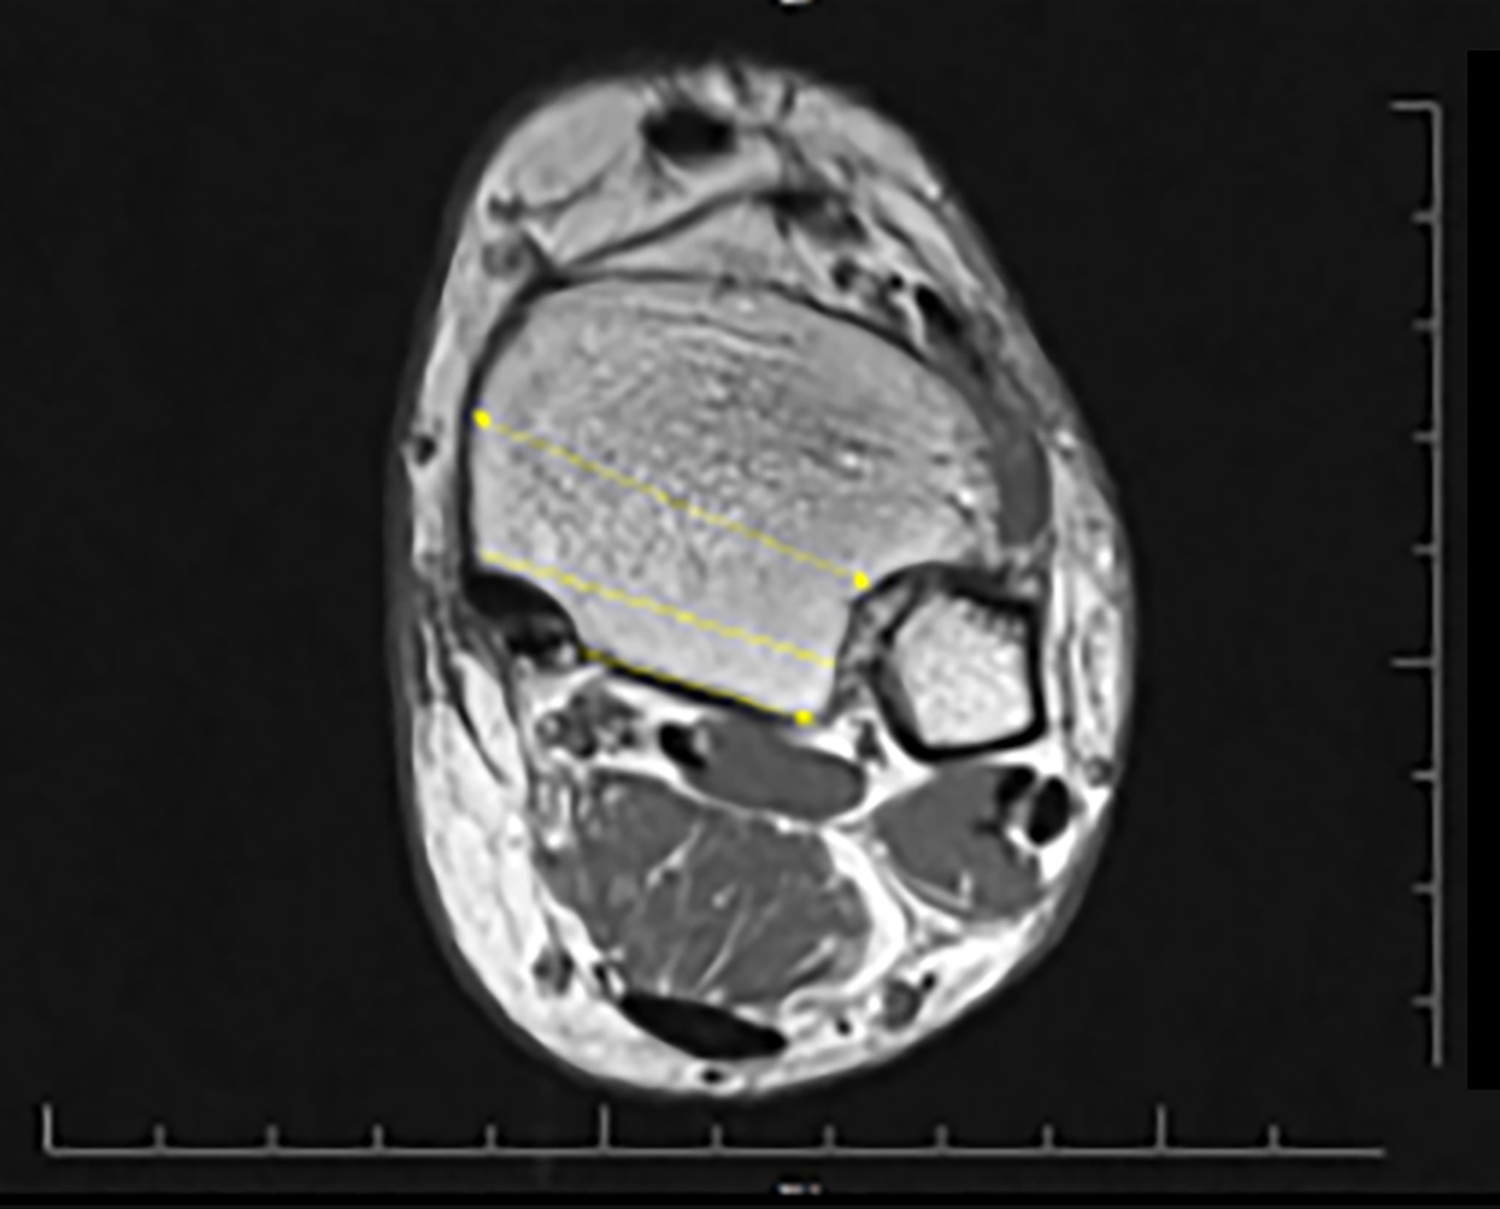

The measurements were performed by the experienced radiologist in musculoskeletal radiology. All the measurements were taken twice and averaged. In ten patients, the measurements were repeated at one-week intervals to investigate intra-observer agreement. In addition, the measurements of 30 patients were also made by a second observer to investigate inter-observer agreement. The MMG depth and width measurements were performed in the axial plane at the level where the groove was the most prominent. The farthest distance between the both edges of the groove was defined as the width, and the vertical distance drawn from this line to the deepest part of MMG was recorded as the depth (Figure 1A). The PTT and FDLT width (transverse measurement) and thickness (anteroposterior length) measurements were undertaken in the same plane (Figure 1B). The groove length was determined on the axial plane images by first determining the MMG start and end levels, and then measuring the distance between the two levels on the sagittal images. The groove opening angle (GOA) was measured as the angle between the two ends of the groove width and its deepest part in the axial plane (Figure 1C). The shortest distance from the posterior border of MMG to the level of syndesmosis articulation in the lateral was recorded as the posterior PM (PPM) length. The total PM (TPM) length was measured from the anterior border of MMG as the shortest distance from the lateral syndesmosis articulation. The measurement performed from the middle part of the tibia, where it was the thickest, was noted as the anterior PM (APM) length. All the three measurements are shown in Figure 2.

Figure 2: Posterior malleolus (PM) measurements. Anterior (single arrow) measurement from the level of the syndesmosis, total PM length measured from the midline (straight line), and posterior PM length measured as the distance from the groove to syndesmosis (double arrow) in the posterior.